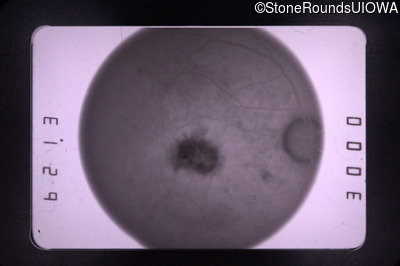

Fluorescein Angiography - Right - 20/30

Exemplar